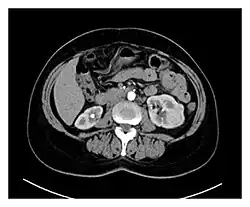

Hypervascularity is an increased number or concentration of blood vessels.